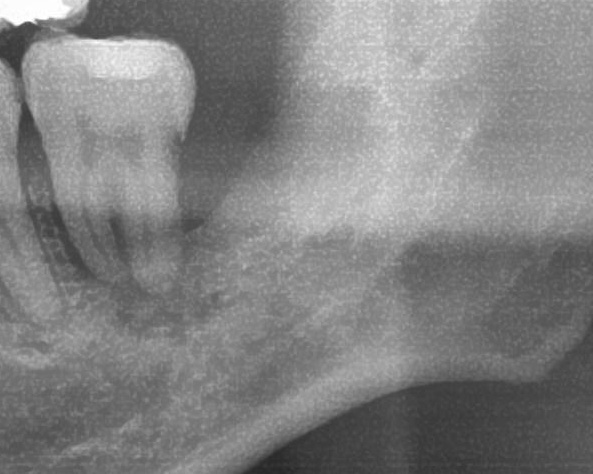

次にパノラマ写真を撮影してみると、左下の親知らずは手前の歯を押すように斜めに生えているのが確認できました。